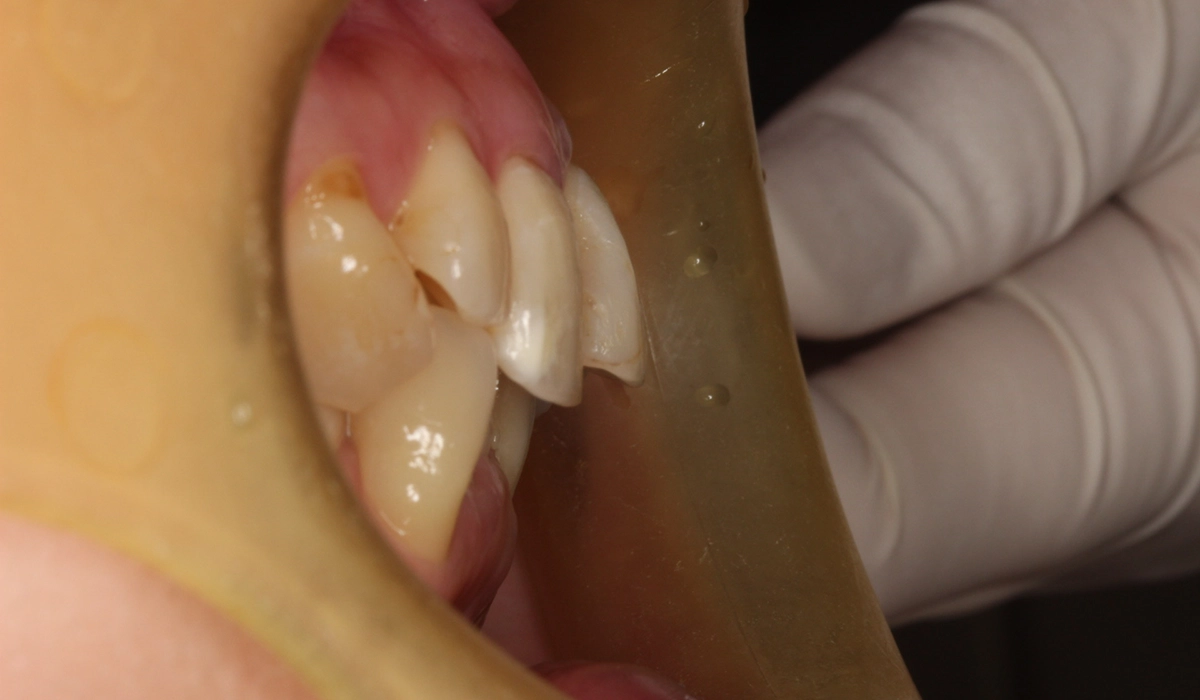

術前:前歯部

術後:前歯部